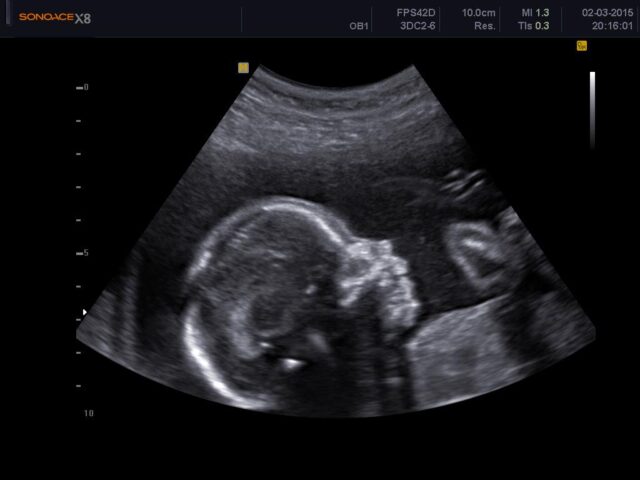

Το υπερηχογράφημα δεύτερου τριμήνου, που συνήθως εκτελείται μεταξύ της 18ης και της 23ης εβδομάδας της εγκυμοσύνης, είναι μια κρίσιμη ιατρική εξέταση που παρέχει λεπτομερείς πληροφορίες για το αναπτυσσόμενο έμβρυο και το αναπαραγωγικό σύστημα της μητέρας. Αυτή η σάρωση, γνωστή και ως «σάρωση ανατομίας» ή «υπερηχογράφημα β επιπέδου », προσφέρει πολύτιμες πληροφορίες για την ανάπτυξη, την ανατομία και τη συνολική υγεία του μωρού.

Κατά τη διάρκεια του υπερήχου δεύτερου τριμήνου, ο γυναικολόγος θα τοποθετήσει ένα ζεστό τζελ στην κοιλιά της μητέρας και θα χρησιμοποιήσει μια συσκευή (κεφαλή του υπερηχογράφου) για να στείλει ηχητικά κύματα υψηλής συχνότητας μέσω της μήτρας. Αυτά τα ηχητικά κύματα αναπηδούν από το μωρό και άλλες δομές, δημιουργώντας εικόνες σε πραγματικό χρόνο σε μια οθόνη.

Την εμβρυϊκή ανατομία: Ένας από τους πρωταρχικούς στόχους είναι η αξιολόγηση της ανατομίας του μωρού, συμπεριλαμβανομένου του εγκεφάλου, της σπονδυλικής στήλης, της καρδιάς, των άκρων και των οργάνων. Αυτό βοηθά στην ανίχνευση τυχόν δομικών ανωμαλιών ή συγγενών προβλημάτων.

Τις μετρήσεις εμβρύου: Η σάρωση μετρά το μέγεθος και την ανάπτυξη του μωρού, συμπεριλαμβανομένης της περιφέρειας της κεφαλής, της περιφέρειας της κοιλιάς και του μήκους του μηριαίου οστού, για να προσδιορίσει εάν η ανάπτυξη αντιστοιχεί στην ηλικία κύησης.